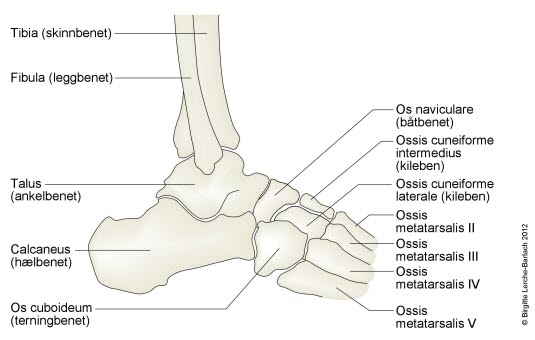

Foten er buet i to retninger, i lengderetningen og tvers over forfoten. Plattfot innebærer at fotbuene er reduserte eller mangler helt. Det skilles mellom en myk type, der det er normal fotbue når pasienten står på tær, og en stiv type der foten er flat hele tiden. Stiv plattfot kan i noen tilfeller gi plager.

Stiv plattfot kan være forårsaket av for eksempel sammenvoksninger mellom ben i foten, feilstillinger av ben, skader og lignende - betegnes derfor også sekundær plattfot.

- Sammenvoksning av knokler i føttene

Plattfot påvises ved undersøkelse av føttene. Den indre fotbuen siger ned mot underlaget når foten belastes. Ved den vanlige myke plattfot får foten normal fasong når trykket avlastes, som for eksempel når man står eller går på tærne. Dette i motsetning til stiv plattfot der foten alltid er flat, for eksempel på grunn av sammenvoksninger mellom ben i foten.

Stiv plattfot fører ofte til plager ved økende alder og økende aktivitet. Spesialtilpassede såler (myke fotsenger) kan være aktuelt ved stiv plattfot. Ved vedvarende plager kan utredning med CT og/eller MR være aktuelt. Ved skjelettskader eller nerve og muskelsykdom kan operasjon i foten være aktuelt.